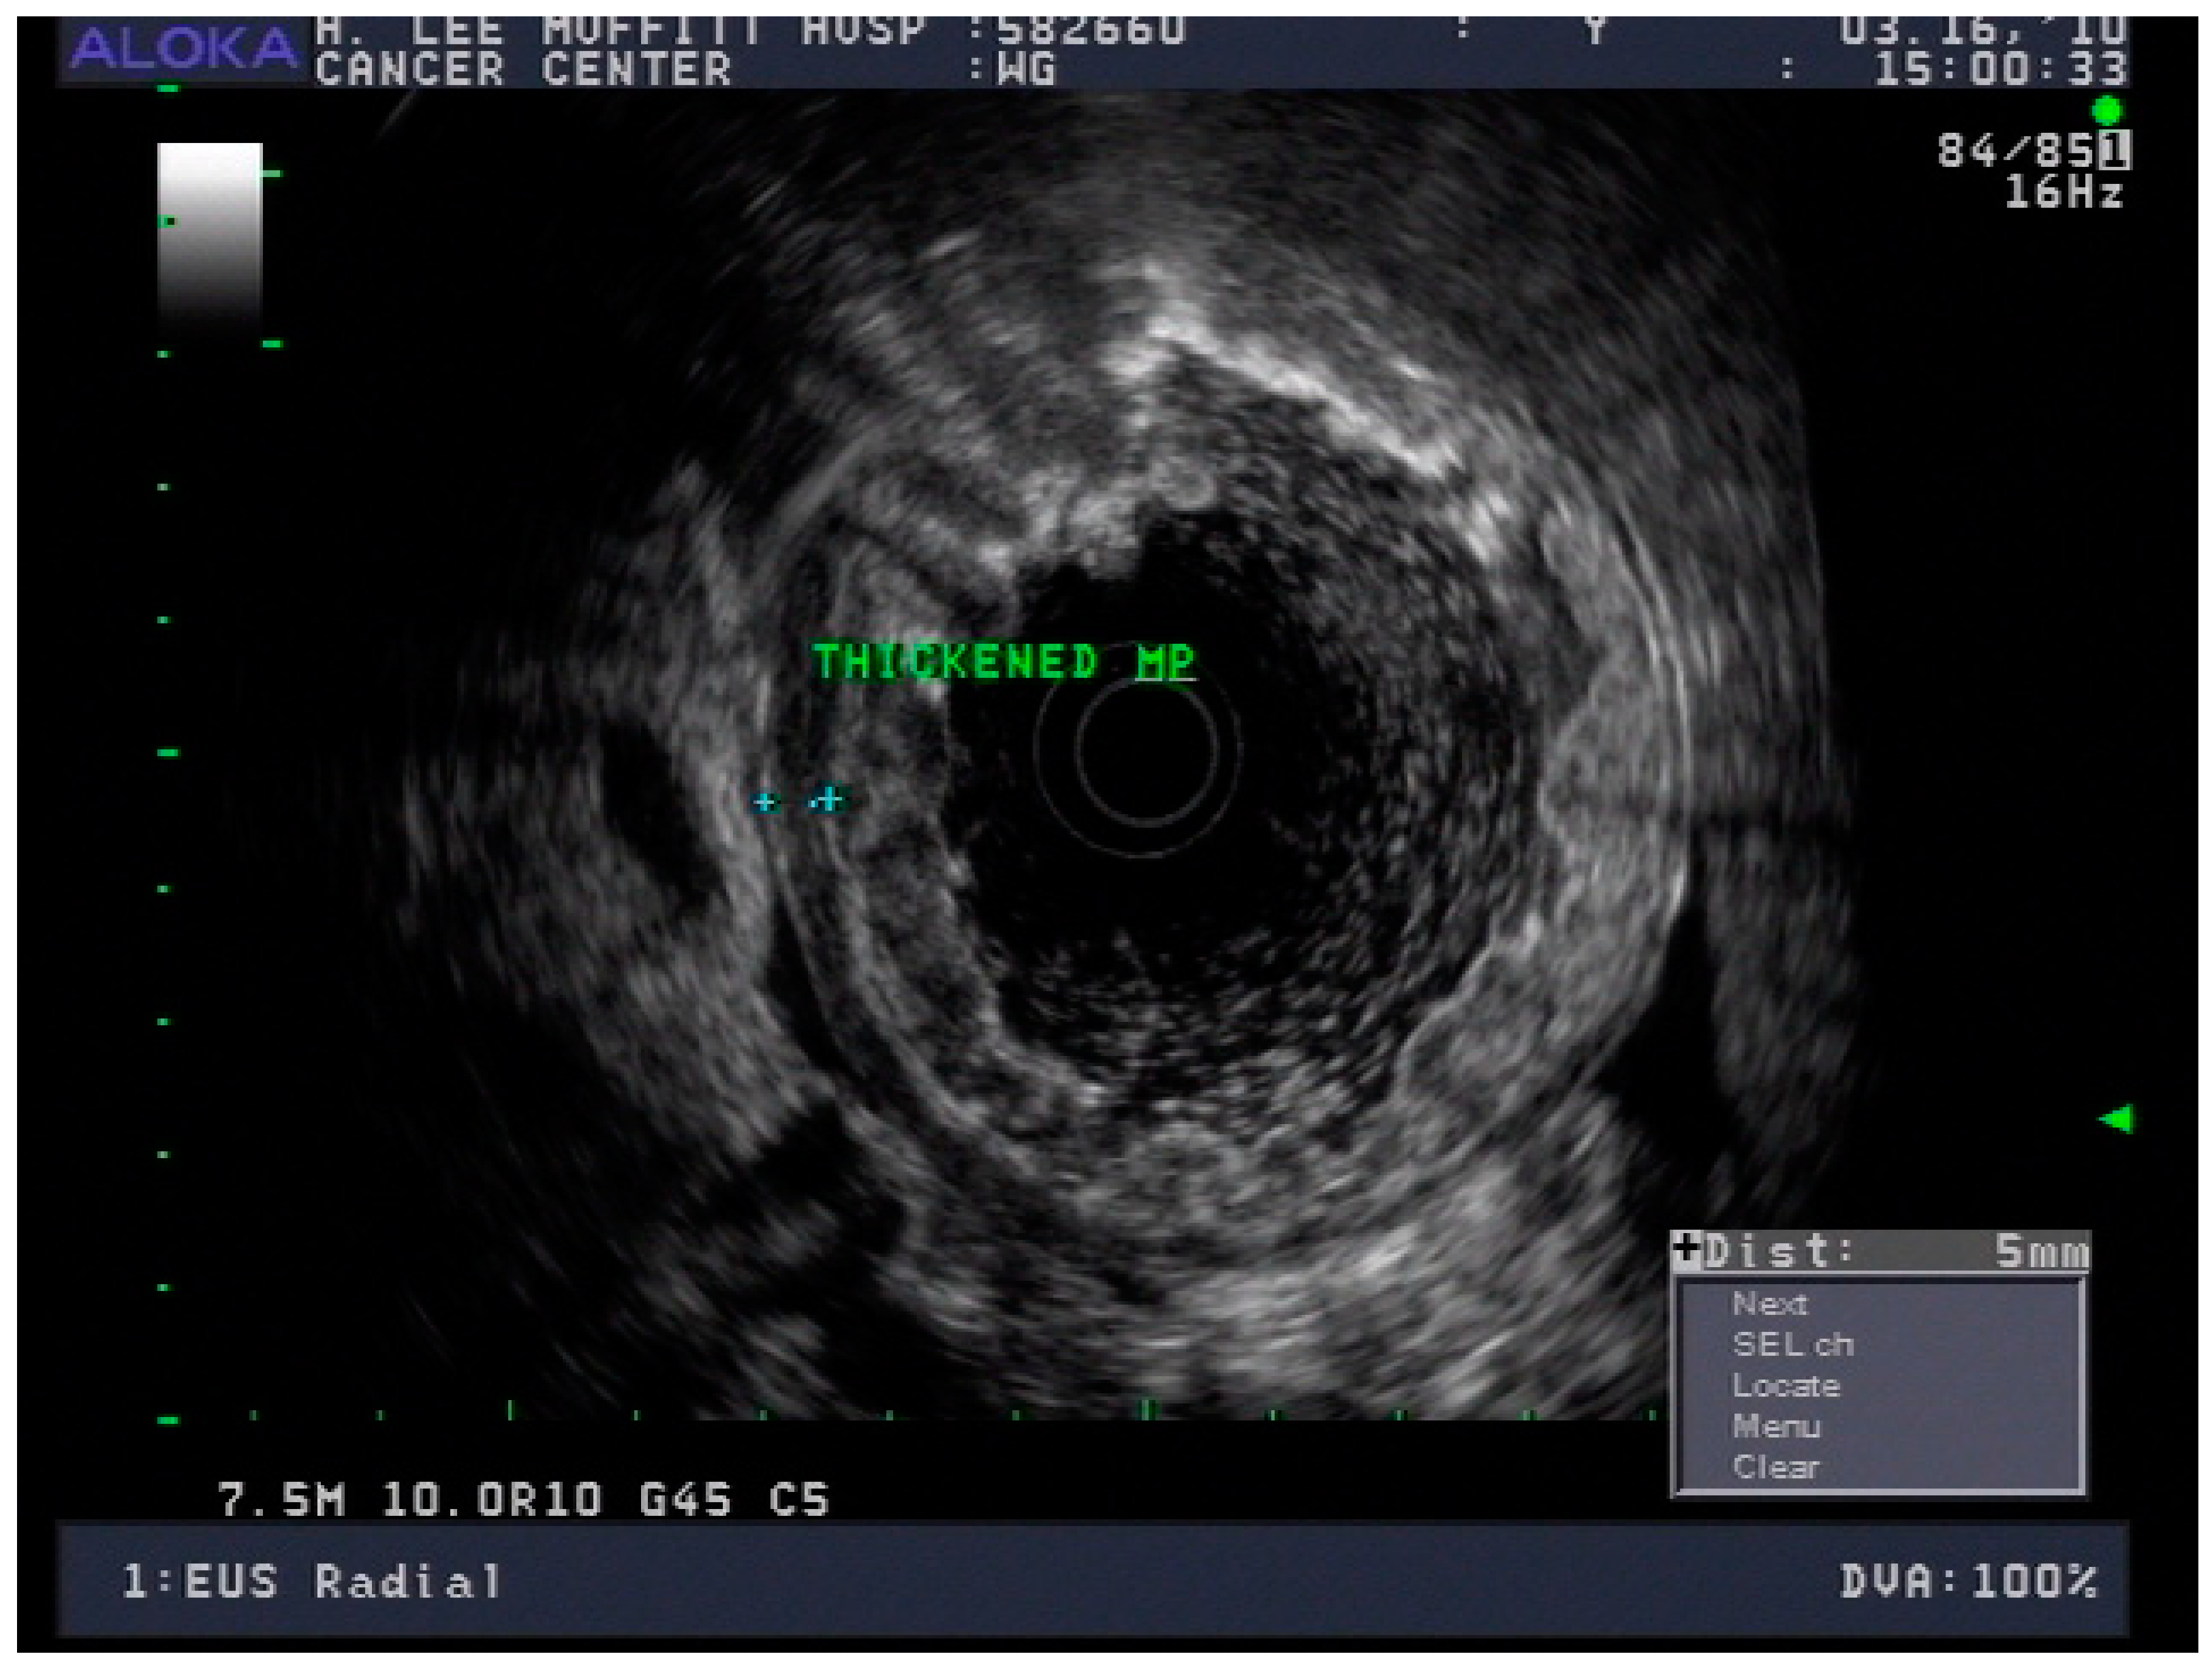

4.3. Endoscopic Ultrasound in Staging of Gastric Cancer

- Spolverato, G.; Ejaz, A.; Kim, Y.; Squires, M.H.; Poultsides, G.A.; Fields, R.C.; Schmidt, C.; Weber, S.M.; Votanopoulos, K.; Maithel, S.K.; et al. Use of Endoscopic Ultrasound in the Preoperative Staging of Gastric Cancer: A Multi-Institutional Study of the US Gastric Cancer Collaborative. J. Am. Coll. Surg. 2015, 220, 48–56. [Google Scholar] [CrossRef] [PubMed]

- Mocellin, S.; Pasquali, S. Diagnostic accuracy of endoscopic ultrasonography (EUS) for the preoperative locoregional staging of primary gastric cancer. Cochrane Database Syst. Rev. 2015, 2015, CD009944. [Google Scholar] [CrossRef]

- Redondo-Cerezo, E.; Martínez-Cara, J.G.; Jiménez-Rosales, R.; Valverde-López, F.; Caballero-Mateos, A.; Jérvez-Puente, P.; Ariza-Fernández, J.L.; Úbeda-Muñoz, M.; López-De-Hierro, M.; De Teresa, J. Endoscopic ultrasound in gastric cancer staging before and after neoadjuvant chemotherapy. A comparison with PET-CT in a clinical series. United Eur. Gastroenterol. J. 2017, 5, 641–647. [Google Scholar] [CrossRef]